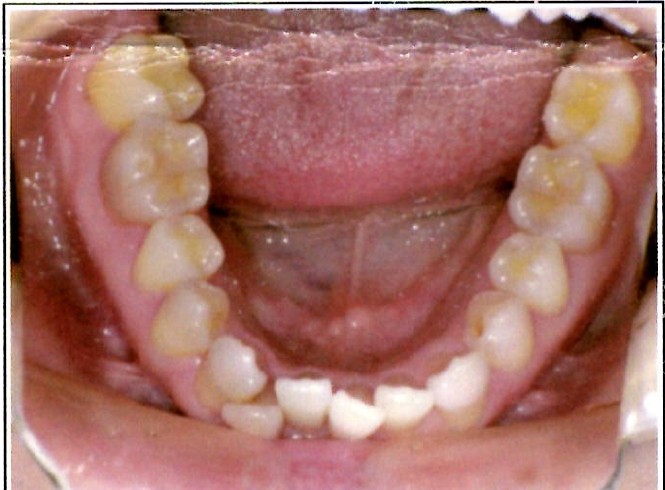

| 主訴・治療前の状態 | 下顎前歯部に叢生(ガタガタ)があり、歯ブラシが届きにくく清掃性に問題がありました。また、見た目も気にされていました。 |

| 治療内容 | 下顎前歯を1本のみ抜歯し、歯列を整えました。治療に際しては、ブラックトライアングル(歯と歯の間の歯茎部分に三角形の隙間ができること)が生じる可能性について事前に説明し、患者様にご了承いただいた上で治療を開始しました。 |

| 治療結果 | 予定通りの仕上がりとなり、事前説明の通りブラックトライアングルは生じましたが、患者様には十分ご理解いただいており、満足度の高い結果となりました。 |